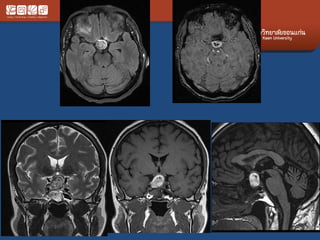

#Germinoma

• 5-25 yrs

• AKA dysgeminoma, intracranail seminoma

• MC at stalk and hypothalamus and pineal

region

• Crawls along floor of the 3rd vent

• Ddx: LCH, craniopharyngioma

• Adult: sarcoid, lymphoma

• If no posterior bright spot  Look at the stalk

and hypothalamus

• Must inject contrast

• DI

– If normal at first

– Please follow up.